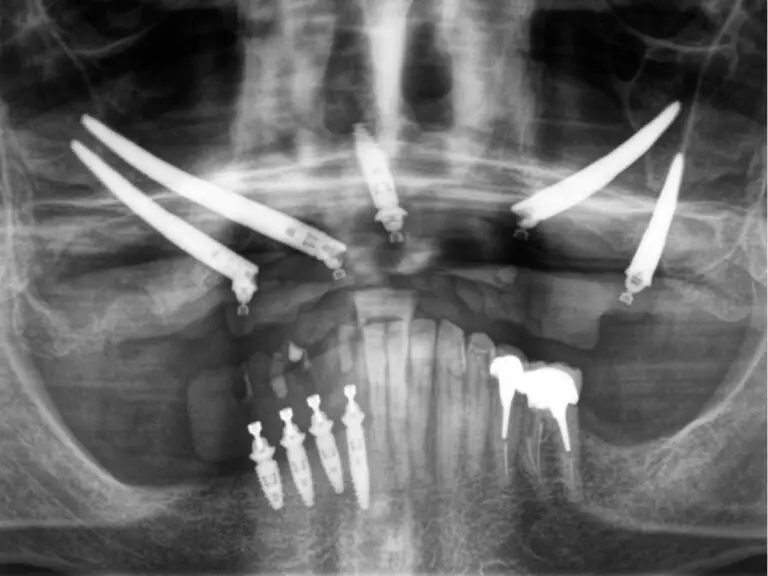

On the right side, two zygomatic implants were placed according to the Quad Zygoma concept, a technique indicated in cases of advanced maxillary atrophy to achieve stable and secure anchorage.

On the left side, two implants were also placed using the ZAGA approach, tailored to the patient’s anatomy and differing from the conventional Quad Zygoma protocol. The second implant was positioned posterior to the zygomatic arch, traversing the infratemporal fossa to engage a denser bone region and extend the posterior support. This configuration increased the anteroposterior (AP) spread and enhanced the stability of the future prosthesis.

Postoperative panoramic X-ray illustrating the final implant configuration, enabling harmonious distribution of occlusal loads and reducing biomechanical stress on the future fixed prosthesis.